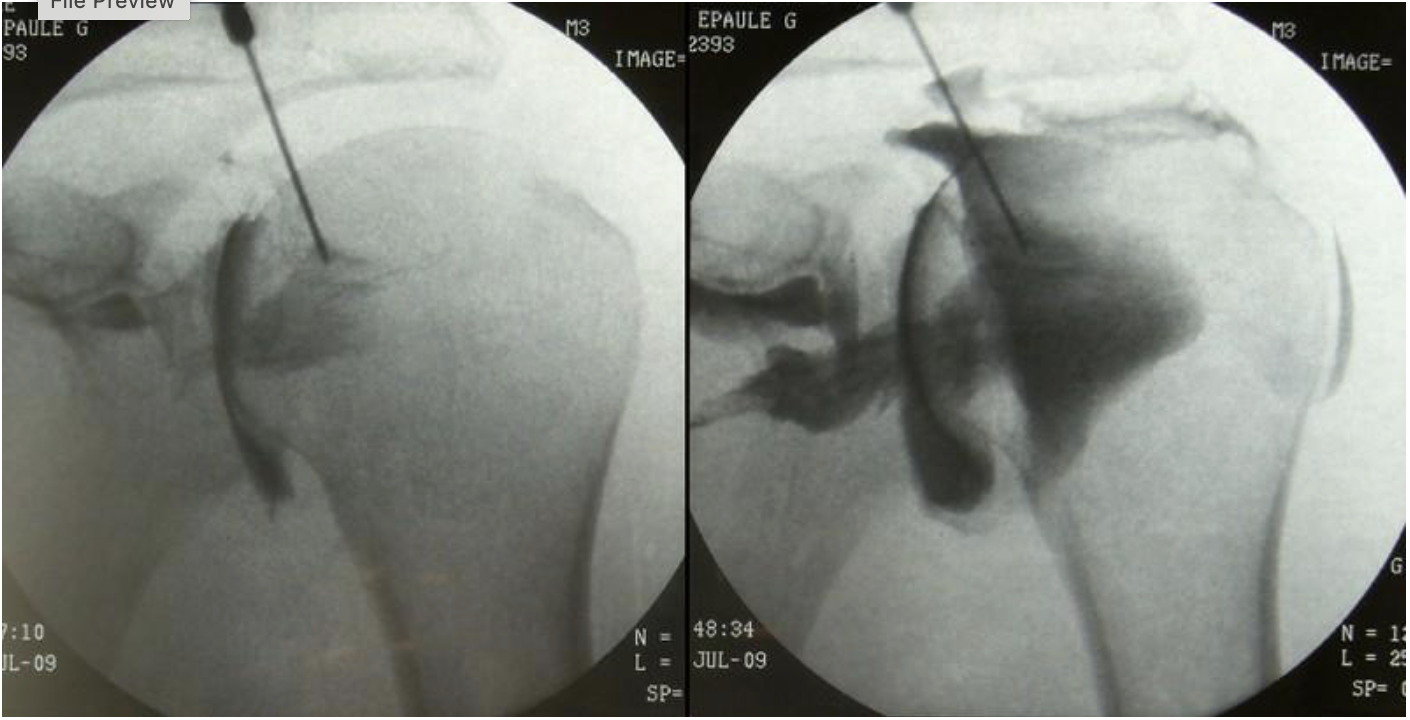

what procedure is being performed

arthrogram of shoulder

what substance is shown as black on this image

radiopaque contrast (omnipaque 300)

what modality will a patient typically go to after having this procedure performed

MRI or CT